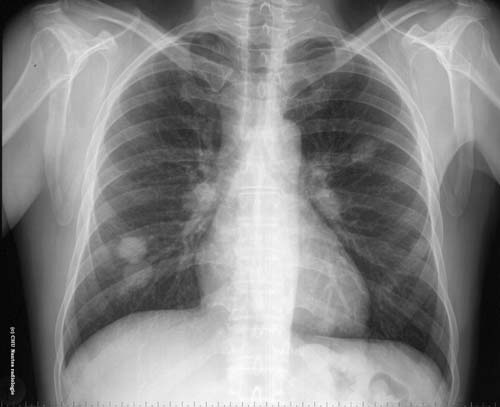

Lésions nodulaires